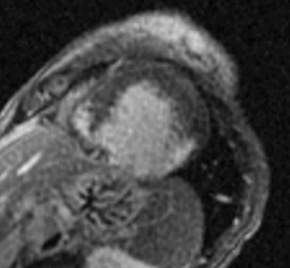

Fig.: 6., 7., 8.: MRI: Extended myocardial infarct of the inferior ventricular wall Late phase contrast enhancement in the thin inferior wall of the ventricle in cross sectional and longitudinal images, MRI

Echocardiography can be used for the detection and follow-up of complications of acute myocardial infarcts. Its great advantage, compared to other modalities, is that it can be performed as a bedside examination, at any time and repeated as often as it is necessary. It can assess the state, the function and the wall motion abnormalities of the left ventricle. Papillary muscle and septum ruptures are also detectable. Furthermore, echocardiography is highly sensitive for the detection of aneurysms, intramural thrombus or pericardial fluid collections. Chronic patients who are stable can usually be controlled by MRI, which in turn provides detailed information.